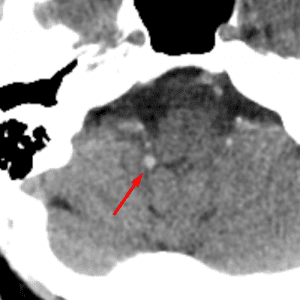

Arachnoid Granulation

Mimicking thrombus